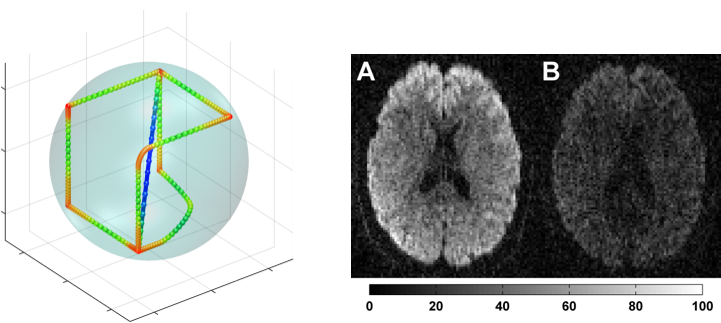

Accelerating linear algebra with graph neural networks Pioneering the use of graph neural networks as a computational primitive for accelerating numerical algorithms. Self-driving labs for accelerated materials science Building autonomous laboratories that combine robotics and AI into closed-loop systems for rapid experimentation and exploration. Diffusion and generative models Developing and applying diffusion-based generative models for image restoration, conditional inference, and scientific applications. Computational medicine Machine learning and optimization for radiotherapy, medical imaging, and clinical diagnostics.